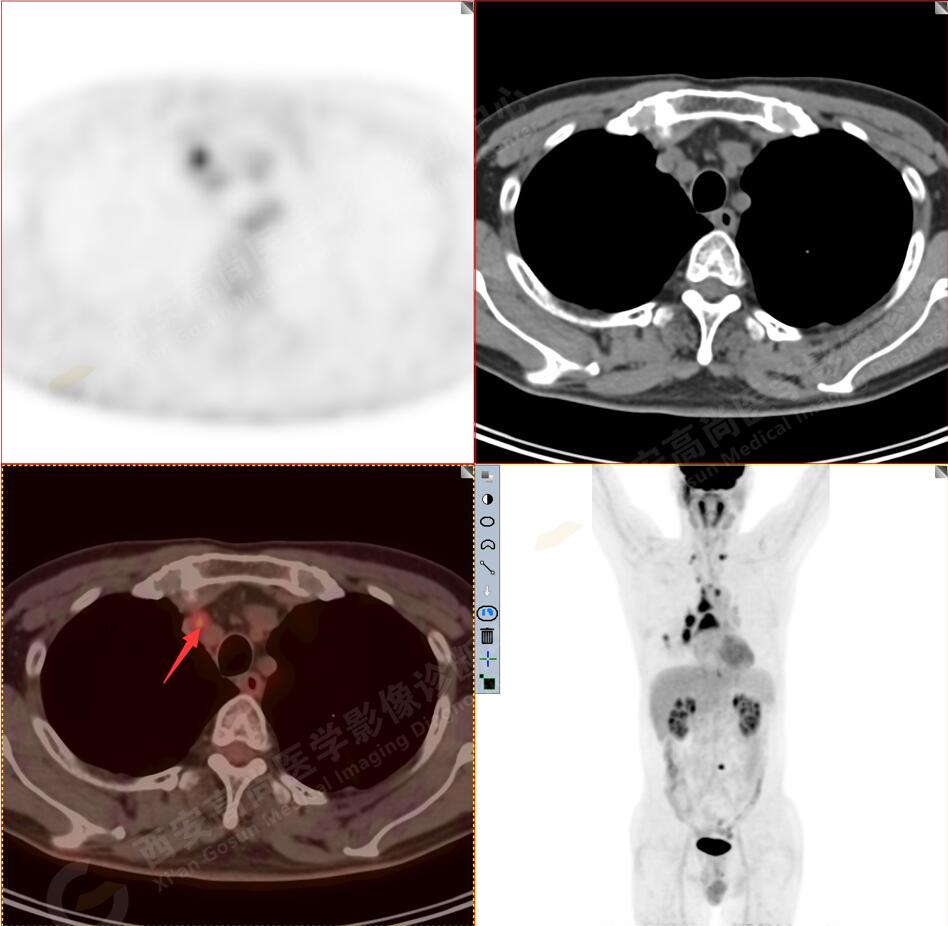

1.以下為肺內(nèi)原發(fā)灶

1.右肺下葉后基底段軟組織結(jié)節(jié)(約1.5cm×1.2cm),與相鄰后胸膜分界不清,呈FDG代謝異常增高,結(jié)合病理,符合肺腺癌伴鄰近胸膜侵犯。